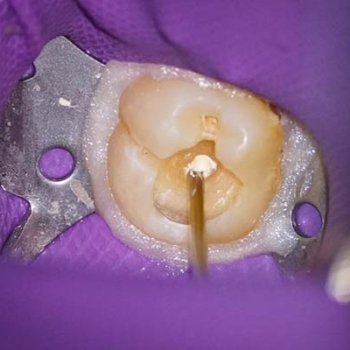

In cases where there is hemorrhaging in the exposed pulp region,  it is necessary to apply sustained pressure for 40–60 seconds with a cotton swab dampened with sterile saline solution (10), followed by the disinfection of the cavity with 0.5% sodium hypochlorite. After this, Biodentine bioactive material was placed to directly cap the pulp (Figs. 5 & 6), the material was placed in bulk increments as a dentinal replacement, as the material sets in 12 minutes, it was possible just to wait until the indicated time and the restoration could be done in the same session (11). The definitive restoration was done afterward, using composite resin with the oblique layer technique (Figs. 7) with the aim of minimizing the contraction of the material (12).

Fig. 5. & Fig. 6. Placing of Biodentine in bulk increments with the help of an endodontic compactor.